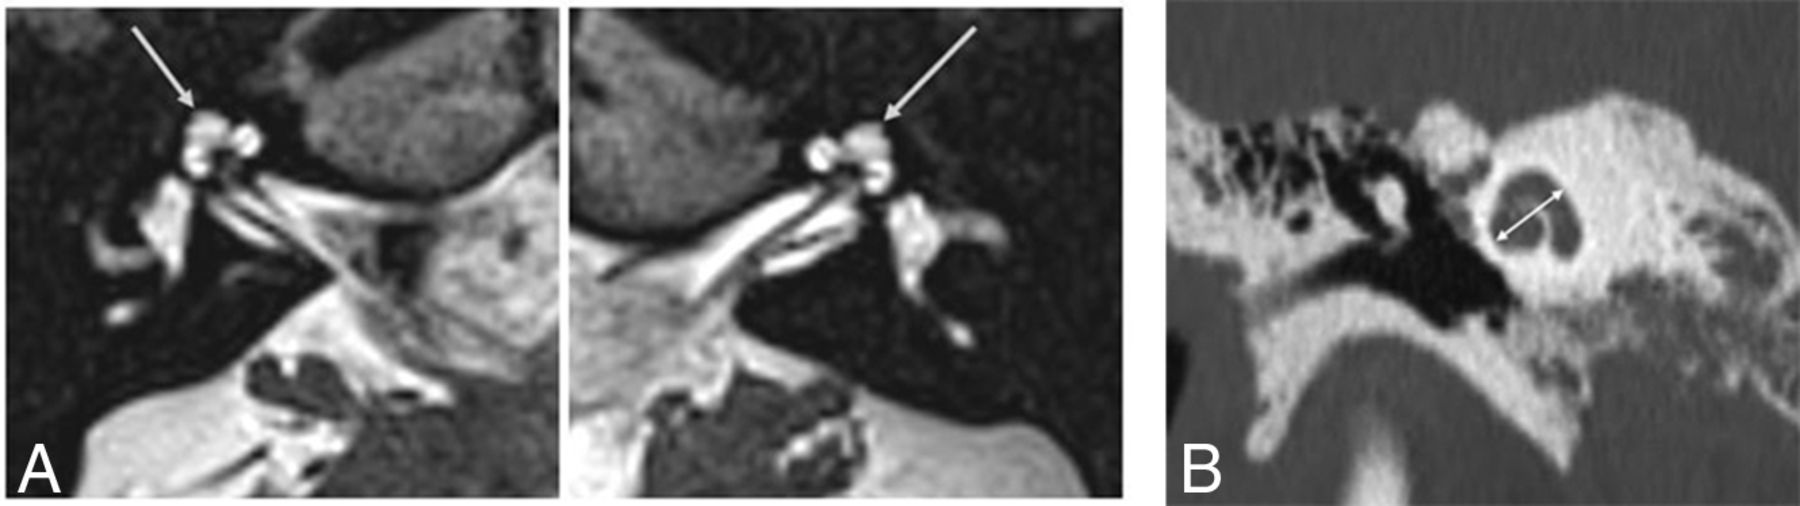

MR imaging of the IAC was performed to investigate the hearing loss. It demonstrated bilateral abnormality of the apical turn of the cochlea, very similar to the “thorny” cochlea described by Pao et al,10 in relation to SIX1 mutation in branchio-oto-renal syndrome (BOR). The cochlear apex was irregular, with a short, stumplike shape (Fig 2). There was mild hypoplasia of the cochlear nerve on the left, but otherwise the inner ear structures were normal bilaterally. The cochlear height was 5.8 and 5.7 mm on the right and left, respectively.

High-resolution 3D heavily T2-weighted MR images of the inner ear and IAC in a patient with a ZNF699 gene mutation. The uppermost turn of the cochlear apex following the middle turn has a short and stumpy shape (arrows).

Searching our institutional archive for genetic malformations, we found, among patients with a genetic diagnosis of BOR syndrome, 3 patients with confirmed SIX1 mutation. Five of these 6 cochleae showed a characteristic “thorny” apical turn, with a small, pointed protuberant appearance (Fig 3). These patients presented with SNHL and other clinical abnormalities expected in BOR due to a SIX1 genetic mutation (ie, otic and branchial defects consistently seen, renal defects variably seen, and less prevalent than among individuals with BOR related to an EYA1 genetic mutation).11 Two of them were previously included in the study by Pao et al.10

High-resolution 3D heavily T2-weighted MR image of a typical SIX1-BOR protuberant “thorny” tip of the cochlea (arrow in A) in comparison with a healthy control in whom the apical turn is uniform and relatively flat and tubular (arrow in B).